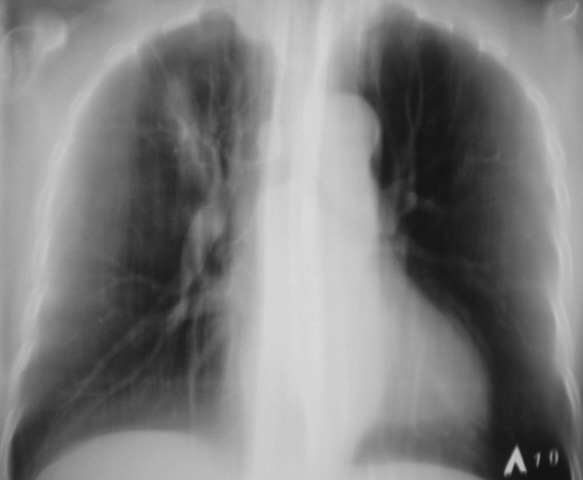

Иллюстрации 1, 2. Произведена рентгенография органов грудной полости в прямой стандартной и правой боковой проекциях. Справа на уровне 1 межреберья дифференцируется крупноочаговая тень овальной формы, от которой в сторону костальной плевры прослеживается линейный тяж. Справа регистрируется усиление и обогащение легочного рисунка. Рисунок правого корня усилен, обогащен, тень его несколько расширена.